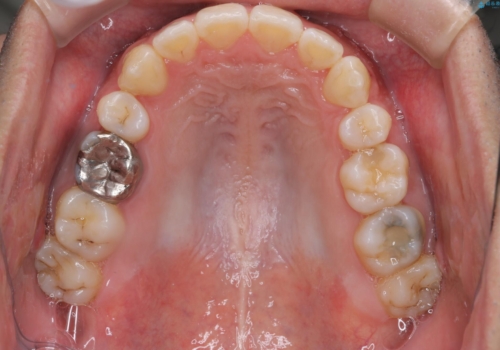

初診時の歯並びの状態としては、右上の犬歯がいわゆる八重歯の状態であり、強いガタガタが上下ともにある状態でした。

スペースの不足量が多く、抜歯を伴うワイヤー矯正にて治療を行いました。

若干の口元の突出感もあったため、抜歯によるスペースを利用し、がたつきの改善と前歯の後退をを行いました。